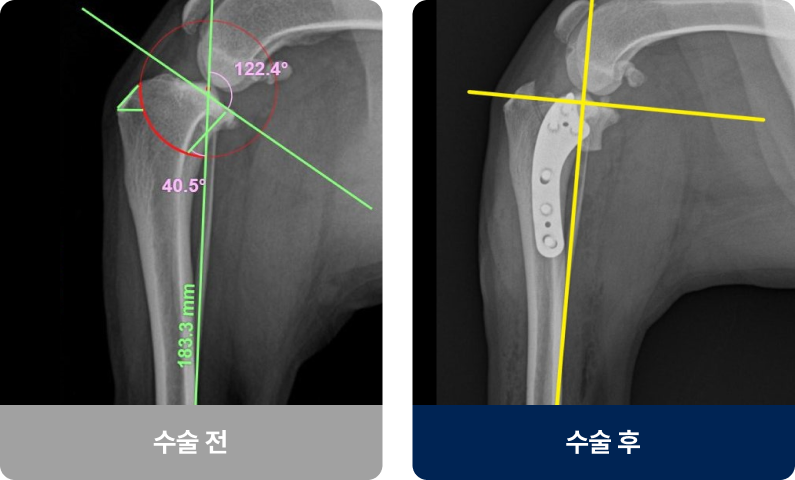

무릎 안에 다리가 앞뒤로 흔들리지 않게 잡아주는 끈이 끊어지거나 부분적으로 손상된 상태로, 중성화된 암컷·대형견일수록 발병률이 높습니다. 주로 급격한 방향 전환이나 높은 곳에서의 점프 등 무릎에 무리가 가는 충격으로 발생하며, 다리를 절거나 들고 걷는 증상을 보입니다.

외과적 치료법(수술적 치료)

끊어진 인대 대신 무릎의 구조적 안정성을 회복하는 것이 목적입니다. 현재는 절골술(TPLO, TTA 등)이 가장 널리 사용되고 있습니다.

끊어진 인대 대신 무릎의 구조적 안정성을 회복하는 것이 목적입니다.

현재는 절골술(TPLO, TTA 등)이 가장 널리 사용되고 있습니다.